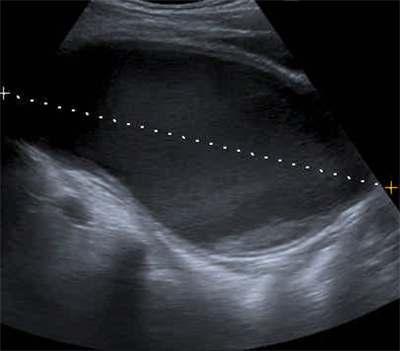

Figure 1

Sagittal US-image showing a large hypogastric mass with hyporeflective content and a small amount of hyperreflective material posteriorly.